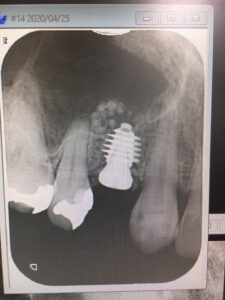

昨日に引き続き、本日は本院にて須田寛昌理事長による、右上4番のソケットリフトオペ

Dr.曰く、骨質が非常に柔らかく近遠心でしか固定取れない為に

径5.5 長さ7ミリのインプラント選択されたそうです

値も狙い通りに☆☆☆!